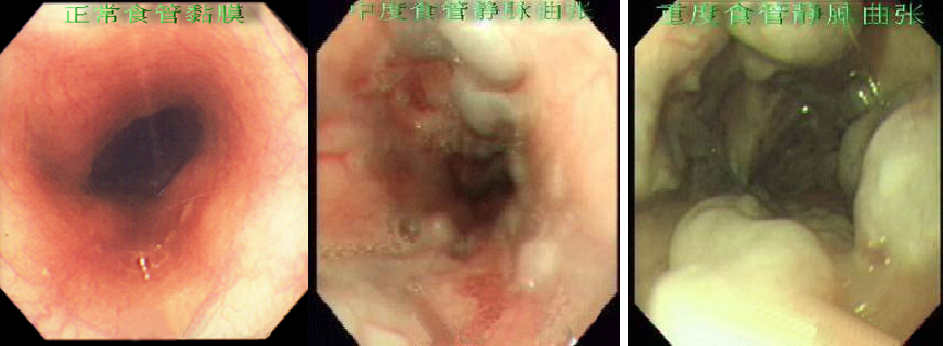

胃镜检查可以评估肝硬化门静脉高压患者食管胃底静脉曲张发生出血的风险(存在、严重程度、有无红色征)等。如门脉高压性胃病,当胃壁淤血、水肿→胃黏膜下层动-静脉支广泛开放→胃黏膜微循环障碍→胃黏膜防御屏障破坏→门脉高压性胃病(粘膜糜烂、出血)。而这可以通过胃镜检查确诊。